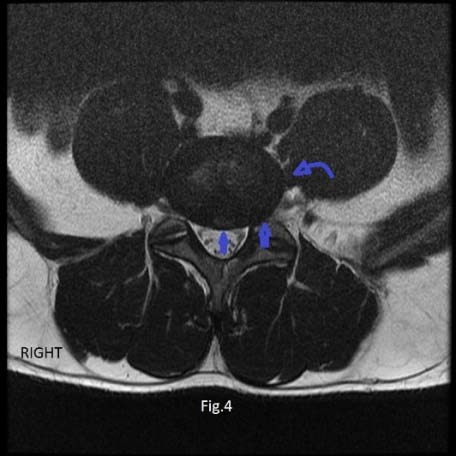

At the L4-L5 disc level, there was the highest prevalence of partial attachment and nonattachment of the PM muscle to the disc. It was seen in 77 (44%) patients. Out of the 77 patients with partial and nonattachment, 45 (79.2%) showed disc herniation (Figure 4); compared with 37 (66.3%) patients out of 98 patients with complete psoas attachment and disc herniation, showing a trend of significance, p value = 0.059.

At the L4-5disc, the PM was partially attached in sixty-seven (38.2%) patients on left side of the disc compared with 63(36%) patients where the PM was partially adhered to the right side of the disc (Fig. 4).